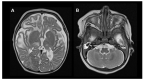

Coenzyme Q10 (CoQ10) is an endogenously synthesized lipid molecule. It is best known for its role as a cofactor within the mitochondrial respiratory chain where it functions in electron transfer and ATP synthesis. However, there are many other cellular pathways that also depend on the CoQ10 supply (redox homeostasis, ferroptosis and sulfide oxidation). The CoQ10 biosynthesis pathway consists of several enzymes, which are encoded by the nuclear DNA. The majority of these enzymes are responsible for modifications of the CoQ-head group (benzoquinone ring). Only three enzymes (PDSS1, PDSS2 and COQ2) are required for assembly and attachment of the polyisoprenoid side chain. The head-modifying enzymes may assemble into resolvable domains, representing COQ complexes. During the last two decades, numerous inborn errors in CoQ10 biosynthesis enzymes have been identified. Thus far, 11 disease genes are known (PDSS1, PDSS2, COQ2, COQ4, COQ5, COQ6, COQ7, COQ8A, COQ8B, COQ9 and HPDL). Disease onset is highly variable and ranges from the neonatal period to late adulthood. CoQ10 deficiency exerts detrimental effects on the nervous system. Potential consequences are neuronal death, neuroinflammation and cerebral gliosis. Clinical features include encephalopathy, regression, movement disorders, epilepsy and intellectual disability. Brain magnetic resonance imaging (MRI) is the most important tool for diagnostic evaluation of neurological damage in individuals with CoQ10 deficiency. However, due to the rarity of the different gene defects, information on disease manifestations within the central nervous system is scarce. This review aims to provide an overview of brain MRI patterns observed in primary CoQ10 biosynthesis disorders and to highlight disease-specific findings.